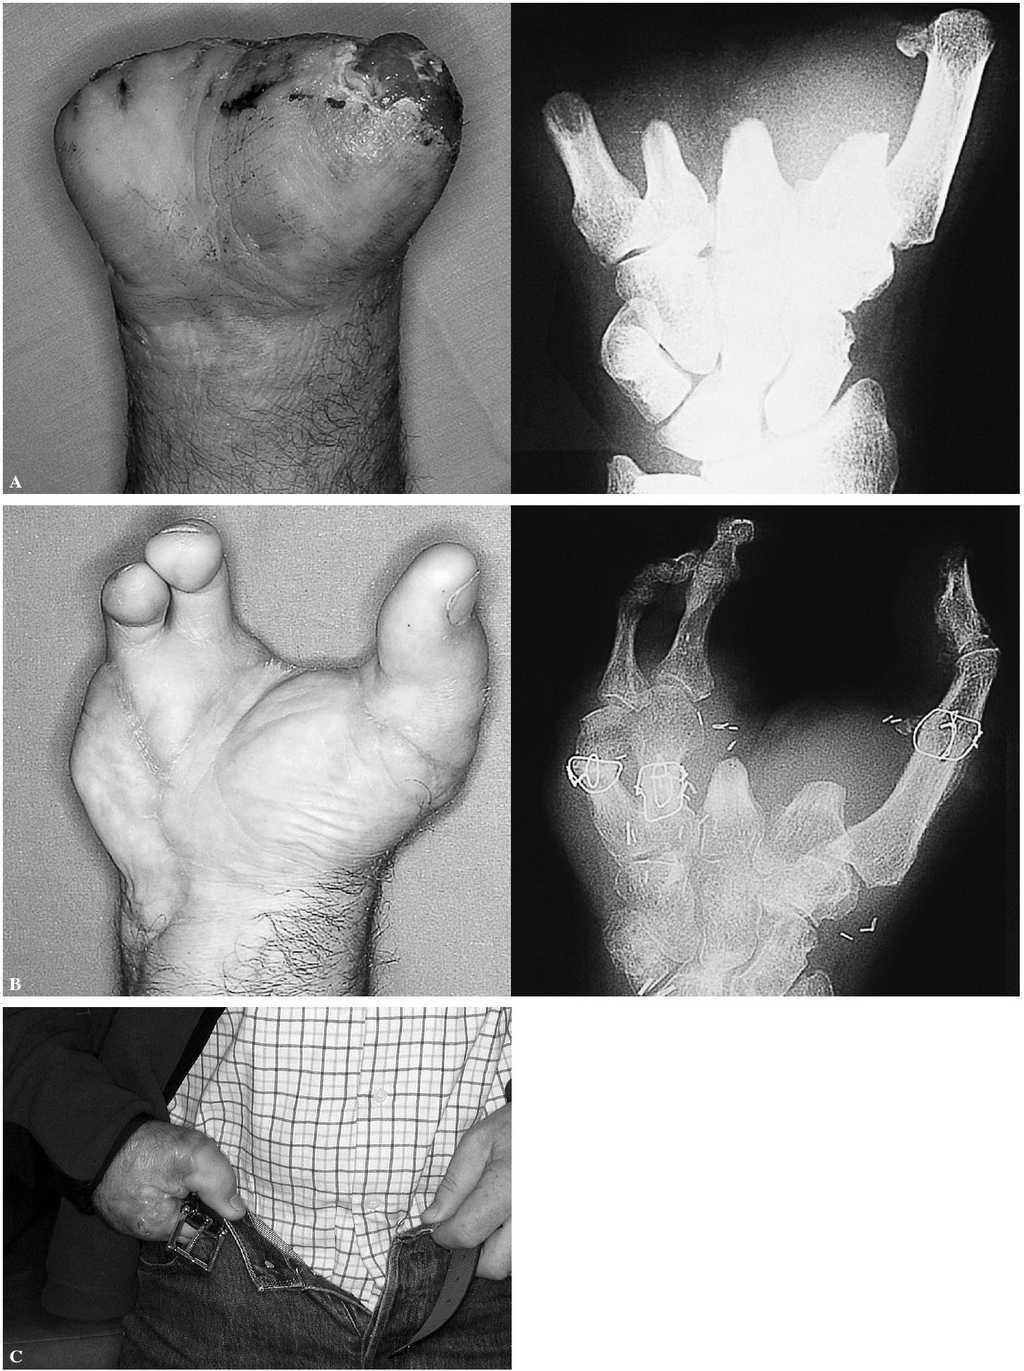

Figura 6. Caso 5. Mano tipo III. A: aspecto preoperatorio. B: resultado a los seis meses de la reconstrucción. Nótese que en este caso se incluyeron las cabezas de los metatarsianos. C: utilización de la mano en tareas básicas a los seis meses de la reconstrucción.